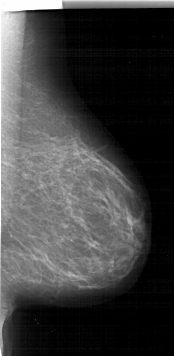

A_1915_1.RIGHT_CC

RIGHT_CC LINES 5401 PIXELS_PER_LINE 3106 BITS_PER_PIXEL 12 RESOLUTION 43.5 NON_OVERLAY